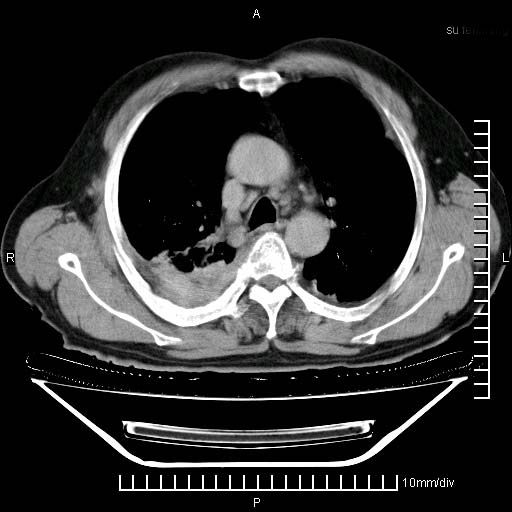

标题: CT24043:胸部增强:男性,60岁

既往肺结核,近10几天,咳嗽,咳痰,右侧胸痛,疼痛较明显,右上肺斑块考虑结核灶胸膜粘连,增强,可惜动脉期没有定好,未见强化,可延迟4分后又见较明显强化,中心见低密度影,如果说结核是边缘强化,可这个灶强化的面积挺大的,让人很挠头。

动脉期